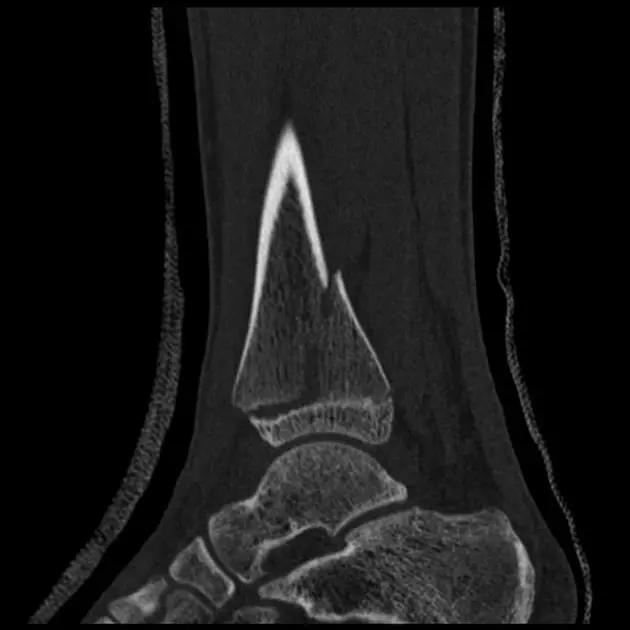

1. 三平面骨折(Triplane fracture )

即累及远端胫骨骨骺的骨折可因骨折线延入其他两个平面而变得复杂,因而称之。骨折由矢状面内的骨骺骨折,经生长板外侧面的轴位面内水平方向骨折,与冠状面内经干骺端到骨干的斜行骨折,自生长板的前侧面伸延至胫骨的后侧皮质。

三平面骨折示意图

图为一 12 岁女孩左踝典型的三平面骨折

三平面骨折 CT 片

三平面骨折 CT 重建